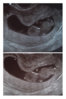

Ultrassa käyty eilen, rv 11+3 ja kaikki kunnossa. :) Ensin ultrasi vatsan päältä ja pelästyin jo kun kuvassa näkyi vain liikkumaton harmaa möykky eikä aluksi mitään sykettäkään, mutta miulla on vain kohtu tosiaan niin takana, ettei mahan päältä näkynyt kunnolla. Alakautta löytyi unilla oleva pieni, jolla kaikki kunnossa. <3

Niskaturvotus saatiin mitattua, mutta kasvoja pikkuinen ei näyttänyt. Esikoinen esitteli aikoinaan nenän ja kaikki, nyt sain nähdä vain takaraivon.

Harmitti, että mies ei päässyt mukaan kun Esikoinen oli kipeä, ja sitten ultrakuvia ei voinut tulostaa mukaan kun paperi oli loppu. Kuvat tulevat postissa ensi viikolla, mutta hormonien vuoksi itkeskelin asiaa illalla. Tosin, eipä niissä kuvissa olisikaan kuin takataivo. ;)